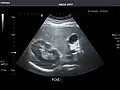

Abdominal ultrasound can be used to diagnose abnormalities in various internal organs, such as the kidneys,[1] liver, gallbladder, pancreas, spleen and abdominal aorta. If Doppler ultrasonography is added, the blood flow inside blood vessels can be evaluated as well (for example, to look for renal artery stenosis). It is commonly used to examine the uterus and fetus during pregnancy; this is called obstetric ultrasonography.[2][3]